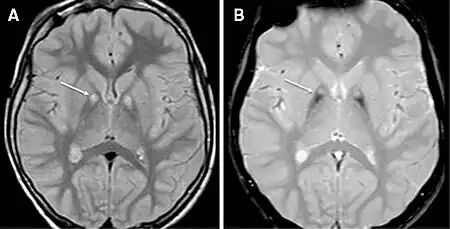

MRI of a individual with pantothenase kinase-associated neurodegeneration | |